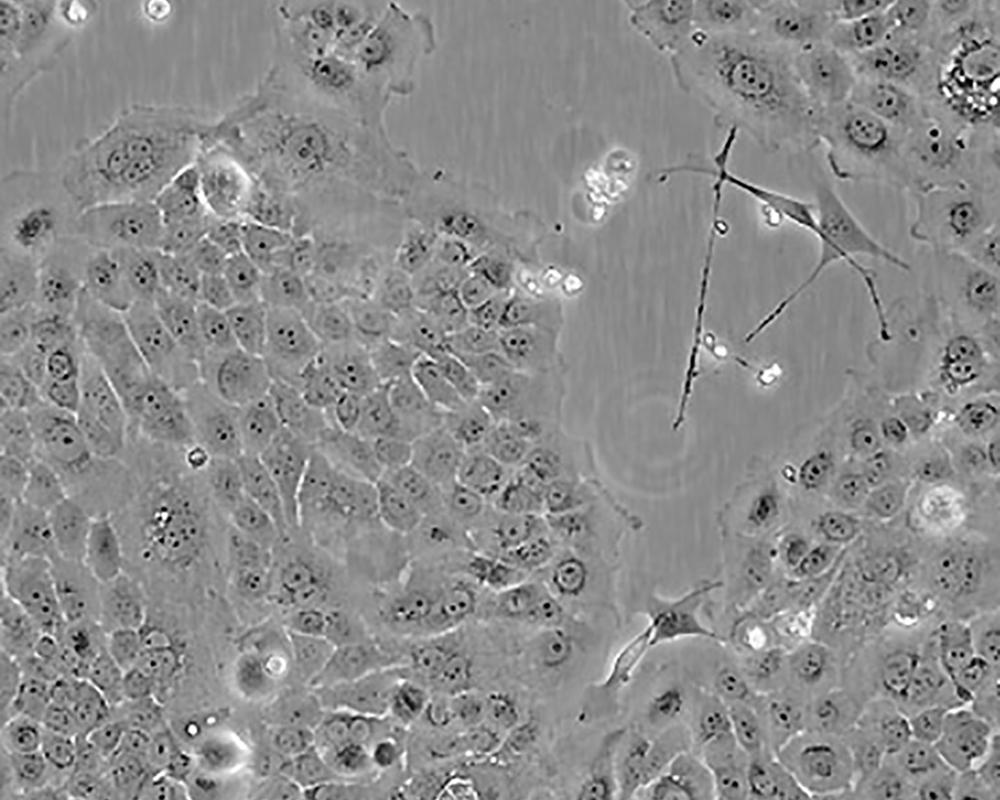

BxPC-3(BxPC3)

產品名稱 BxPC-3(BxPC3)

中文名稱 人原位胰腺腺癌細胞

組織來源 胰腺導管腺癌;女性

生長特性 adherent

形態特征 epithelial

細胞描述 The cells do not express the cystic fibrosis transmembrane conductance regulator(CFTR). A CFTR positive pancreatic line, Capan-1 is available.